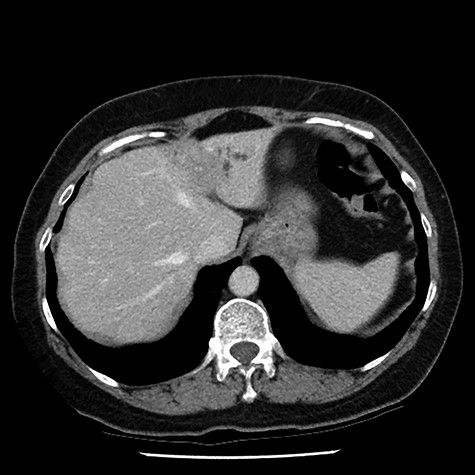

A 54-year-old female, of Philippines descent, presented to our department following the incidental discovery of a 23 × 20 mm ill-defined mass within segment II/III of the liver during ultrasound workup for mildly deranged liver function tests. She had no symptoms from the lesion, and she reported no significant past medical history. A pre- and post-contrast multiphase helical computed tomography identified a 26 × 25 mm ill-defined region of hypodensity, with a small focus of central calcification, within segments II and III of the liver (Fig. 1). The lesion was causing biliary obstruction indicated by dilatation of the intrahepatic biliary ducts within the entire left lobe of the liver and appeared to be in continuity with the left hepatic duct. Magnetic resonance imaging of the liver identified an irregular enhancing mass within segment IV that had a central area of non-enhancing low signal intensity (Fig. 2). As a part of the patient’s workup for presumed malignancy, an upper and lower endoscopy, bilateral mammogram and ultrasound assessment of the breasts were all found to be normal. A biopsy was not able to be obtained due to the proximity of the lesion to the porta hepatis.

post-contrast multiphase helical computed tomography identified a 26 × 25 mm ill-defined region of hypodensity, with a small focus of central calcification, within segments II and III of the liver